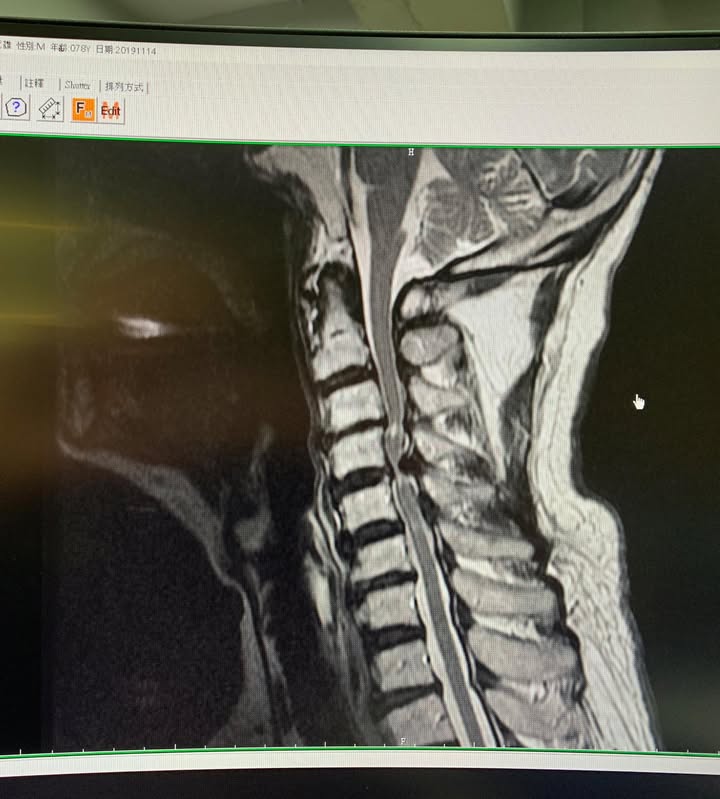

Cervical Spine Treatment Cases 頸椎治療案例 感謝新竹市羅小姐熱情見證 頸椎整合中醫微創療法逆轉勝 2020.03.18 感謝台北市👮♀️陳大哥熱情見證 困擾三年頸椎疼痛逆轉勝 騎機車手麻到無法煞車劇痛不... 2020.03.13 感謝台中市許大姐熱情見證 頸椎壓迫導致右臂酸麻痛五個月 脊椎整合中醫微創逆轉勝 2020.03.12 史上第一次碰到全聾啞人士聘用手語翻譯人員來診所接受脊椎整合中醫維創! 2020.02.22 #嚴重的頸椎反弓醫案 #疼痛超過半年左側肩膀麻痛連手臂 #感謝葉先生熱情見證 2020.02.22 #頸椎痛到無法睡覺怎麼回事 #神經根型頸椎病醫案 #感謝台北吳小姐熱情見證 #脊椎整合... 2020.02.13 #頸椎間盤突出痛到右手完全沒力 #神經根型頸椎病合併輕微脊髓壓迫 #原本考慮裝設人工... 2020.02.07 #脊髓型嚴重壓迫患者 #可能非針刀類型患者 2020.01.23 #頸椎壓迫醫案見證 #脊椎整合中醫微創療法原理說明 #感謝新竹余先生熱情見證 #什麼症... 2020.01.22 #頸椎壓迫神經根醫案 #疼痛超過三年以上 #來診前幾個月大痛到無法睡覺 #感謝新莊陳大... 2020.01.10 #感謝台大學長熱情見證頸椎針刀療法 #脊椎整合中醫微創療法 2019.12.17 #感謝宜蘭李大哥熱情見證 #神經根型頸椎病痛到上臂肩膀麻痛 #原本想說熱愛的衝浪可能... 2019.12.08 😂原本都準備要去開刀了! 😢醫學中心報價兩節椎間盤報價52萬 😄感謝苗栗患者熱情見證... 2019.11.22 ❇️頸椎間盤突出痛到完全無法洗頭 #核磁共振證實C4C5突出壓迫 #上樓梯頭往後面抬就誘發... 2019.11.13 #頸椎痛到無法睡覺怎麼回事 #原本認真考慮開刀治療 #感謝雲林患者熱情北上見證 #脊椎... 2019.10.21 ← 上一頁 6 7 8 9 10 下一頁 →